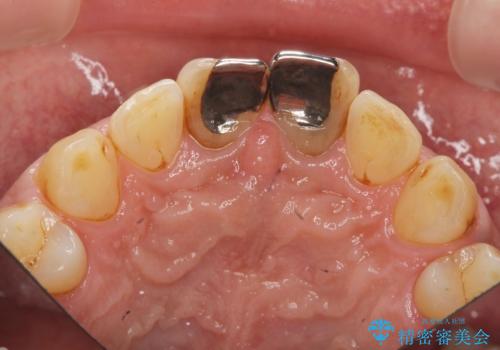

- 体調により前歯部の歯ぐきから出血や膿が出ることの改善を求めて来院されました。

X線写真より、根尖部に透過像が認められ根管治療・ファイバーコア築盛・セラミッククラウンの作製が必要な状態です。